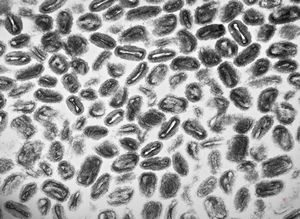

F, 7y. | molluscum contagiosum … virions

F, 7y. | molluscum contagiosum … virions

F, 24y. | molluscum contagiosum … virions